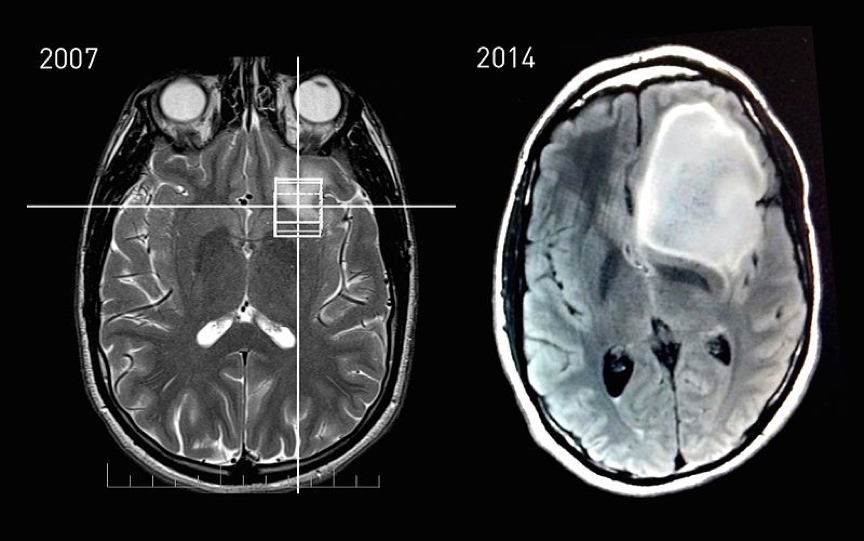

3. Glioblastoma Multiforme (GBM)

- Origin: High-grade astrocyte tumour

- Macro: Supratentorial, solid with possible cysts

- Features:

- Rapid progression, severe headache, seizures

- Personality changes, hemiparesis

- Treatment: Palliative (surgery + chemo/radiotherapy + corticosteroids)

- Prognosis: Poor (<1 year median survival)